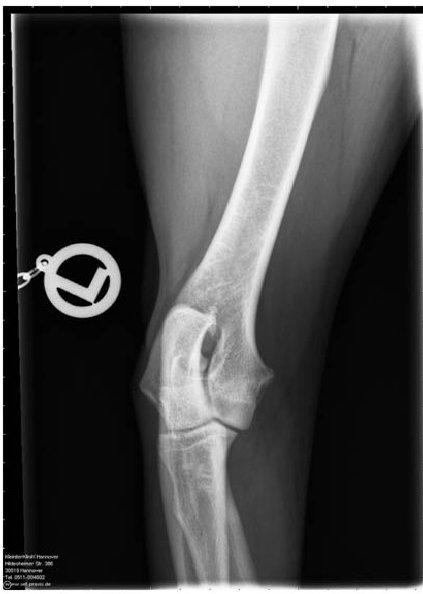

ED - OCD - Röntgenaufnahme